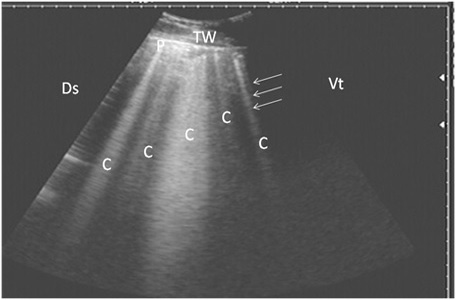

Ultrasonography of pulmonary emphysema in 9 cows using a 3.5 MHz transducer. The image shows multiple comet-tail artifacts in the form of bright echogenic bands (white arrows, C), pleura (P) and the thoracic wall (TW). The right part of the image is ventral (Vt) and the left is dorsal (Ds).